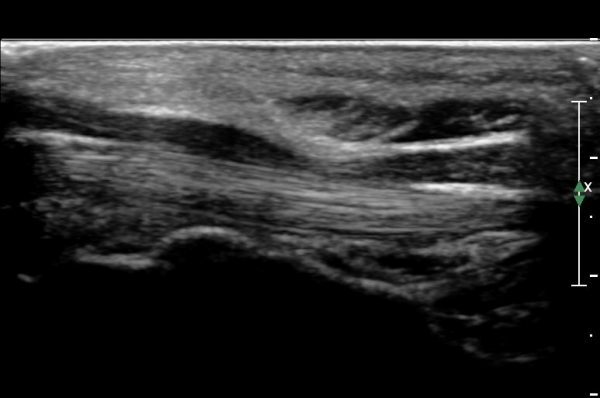

¼ö±Ù°ü ±ÙÀ§ºÎ(scaphoid, lunate level)¿¡¼ Á¤Á߽Űæ Ⱦ´Ü¸é°Ë»ç»ó Á¤Á߽ŰæÀÇ Àú¿¡ÄÚ ºÎÁ¾ÀÌ °üÂûµÊ.(»çÁø 2).